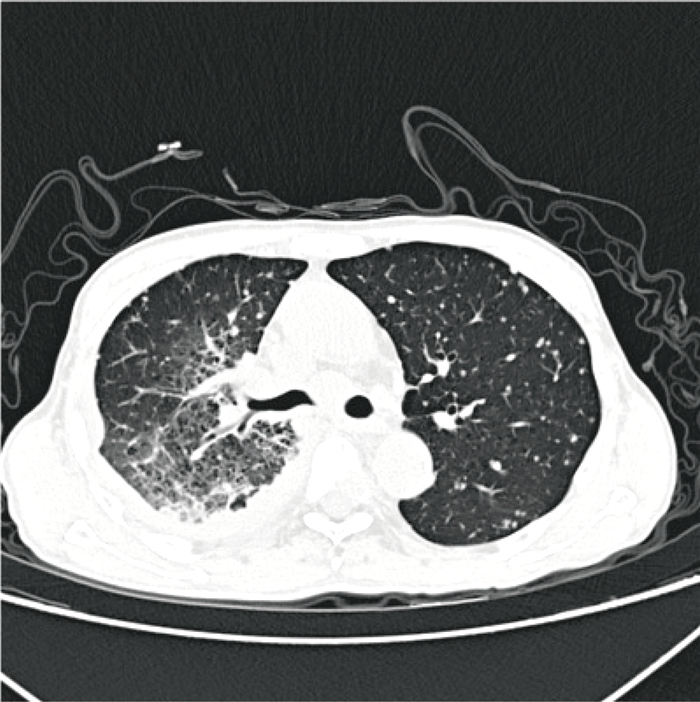

1.2 检查结果 1.2.1 实验室检查入院辅助检查显示:白细胞计数10.51×109/L,中性粒细胞计数6.82×109/L,超敏C反应蛋白11.07 mg/L,血清淀粉样蛋白17.04 mg/L。胸部计算机断层扫描术(computer tomography,CT)结果如图 1所示,患者右上肺门肺癌伴右肺门及纵隔淋巴结转移,右侧胸腔积液,右肺部分膨胀不全,双肺多发转移瘤,胸骨及胸椎转移,双侧锁骨上淋巴结转移。初步诊断为肺恶性肿瘤并伴有肝、骨、淋巴结、胸膜转移。

| 图 1 患者入院时胸部CT征象 Fig. 1 Chest CT signs on patient admission |